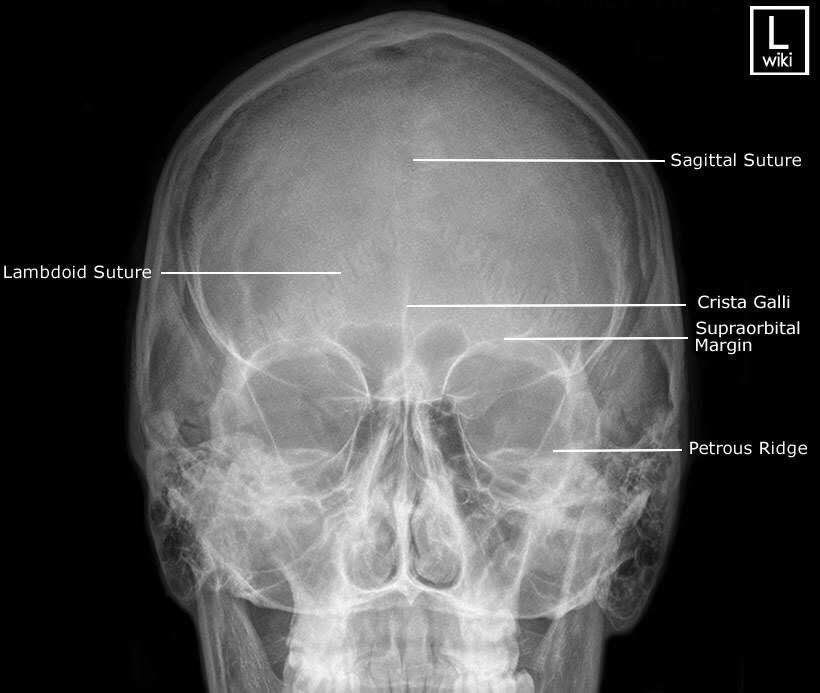

Las radiografías, generalmente llamadas rayos X, producen imágenes como sombras de huesos y ciertos órganos y tejidos. Las radiografías son muy buenas para detectar problemas óseos. Pueden mostrar algunos órganos y tejidos blandos; sin embargo, la MRI y la CT suelen crear mejores imágenes de los mismos. Aun así, las radiografías son rápidas, fáciles de obtener y menos costosas que los otros estudios, por lo que se pueden usar para obtener información rápidamente.

Un tubo especial dentro de la máquina de rayos X emite un haz de radiación controlada. Los tejidos del cuerpo absorben o bloquean la radiación en diferentes grados. Los tejidos densos como los huesos bloquean la mayor parte de la radiación, pero los tejidos blandos, como la grasa o los músculos, bloquean menos radiación. Después de pasar por el cuerpo, el haz alcanza una pieza de un fragmento de película o un detector especial. Los tejidos que bloquean altas cantidades de radiación, como los huesos, aparecen como áreas blancas en un fondo negro. Los tejidos blandos bloquean menos radiación y aparecen en tonos de gris. Los órganos que contienen principalmente aire (como los pulmones) aparecen en negro. Los tumores son por lo general más densos que el tejido que los rodea, por lo que suelen verse en tonos grises más claros.